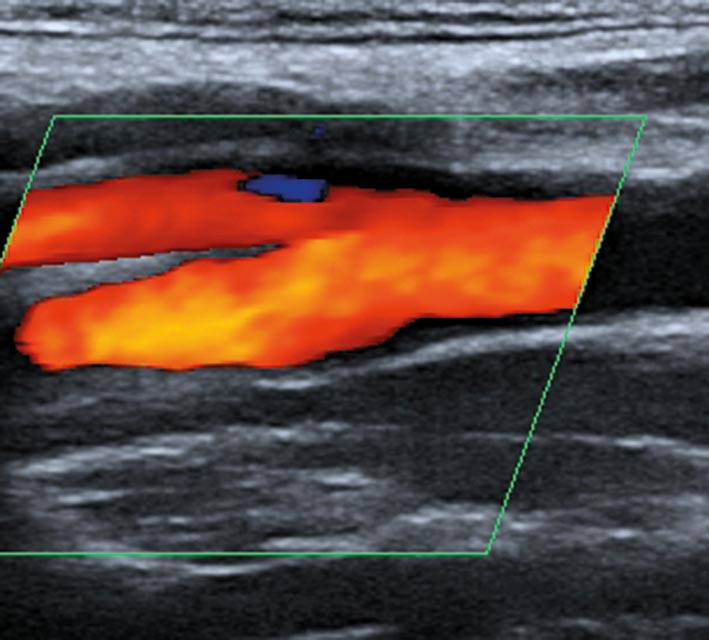

Ultraschallbild der inneren und äußeren Halsschlagader

Die Ultraschalluntersuchung (farbkodierte Duplexsonografie) ist hierbei die wichtigste Untersuchung, da sie sehr aussagekräftig, leicht wiederholbar und ungefährlich ist.